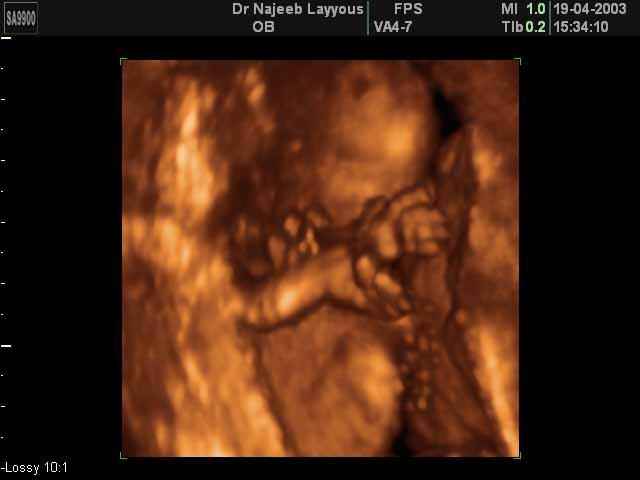

- صور لأطراف الجنين

- صور لتصرفات الجنين داخل الرحم

صور لأطراف الجنين بجهاز الالتراساوند ثلاثي الأبعاد | الدكتور نجيب ليوس